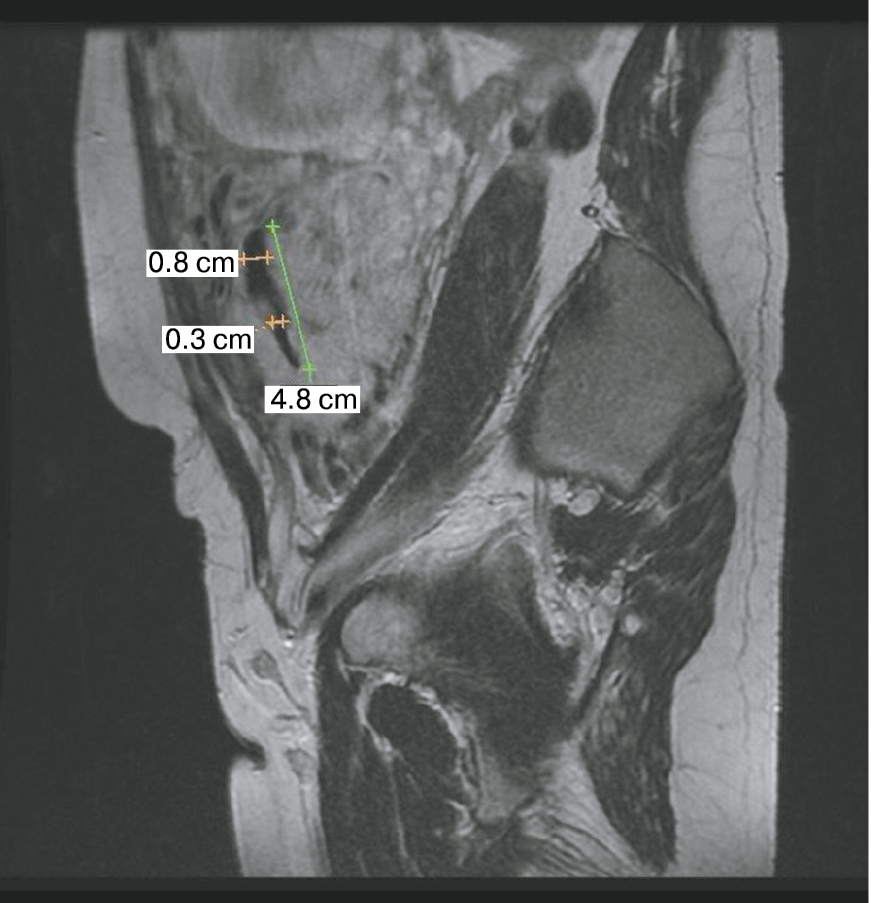

Также стоит выделить особый тип плацентарной гиперваскуляризации, а именно включение в плацентарной ткани изменений по типу «обнаженного сосуда» (рис. 1, 2). Мы провели анализ встречаемости данного признака среди наших пациентов. Любопытным наблюдением явилось то, что данный симптом в нашей выборке встречался только при наличии placenta percreta – 6 случаев, а именно при поражении параметриев, и не встречался при плацентарной инвазии, ограниченной миометрием. «Мостовидные сосуды» были менее специфичны, тем не менее, их наличие также сопровождало тяжелые формы врастания, обусловленные более глубокой инвазией ворсин хориона, – 8 случаев.

Рис. 1. МРТ placenta percreta, симптом «обнаженного сосуда»

Рис. 2. МРТ placenta percreta, симптом «обнаженного сосуда»

Является ли симптом «обнаженного сосуда» патогномоничным для параметральной инвазии или нет, еще предстоит выяснить; однако в ходе исследования установлена его связь с частотой гистерэктомий в группах с наличием симптома «обнаженного сосуда», что, вероятно, обусловлено мощной сосудистой сетью коллатералей и неоангиогенезом. Во всех случаях обнаружения данного признака впоследствии была выполнена вынужденная гистерэктомия (рис. 3–6, пациентка Н., 37 лет).